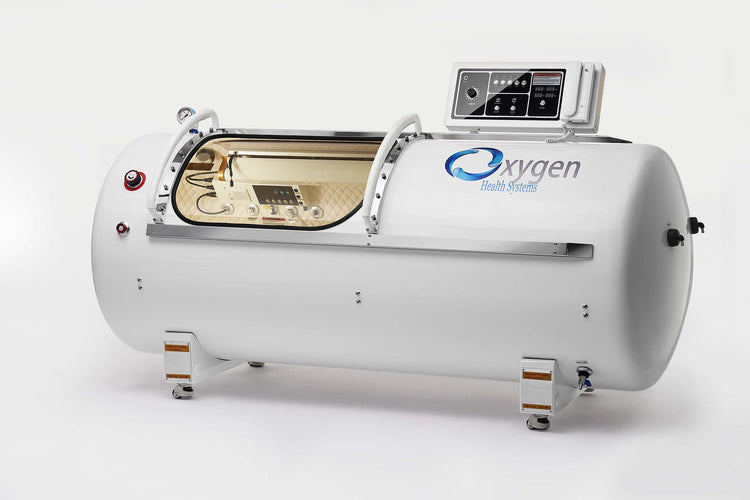

36-Inch Hard Shell Hyperbaric Oxygen Chamber supports 2.0 ATA (100 kPa) pressure and 15 PSI. Built with 2.5 mm thick 304-grade stainless steel and a 10 mm thick polycarbonate window from Bayer Germany. Designed with heavy-duty steel rods and ball-bearing rollers for smooth movement. Features incremental control of pressurization and depressurization, interior and exterior emergency pressure relief valves, interior lighting, and an alarm system. Allows auto-controlled session times up to 2 hours with a timer and offers an optional progressive control feature. Chamber dimensions are 88 inches in length and 36 inches in diameter. Includes a 3-year warranty.